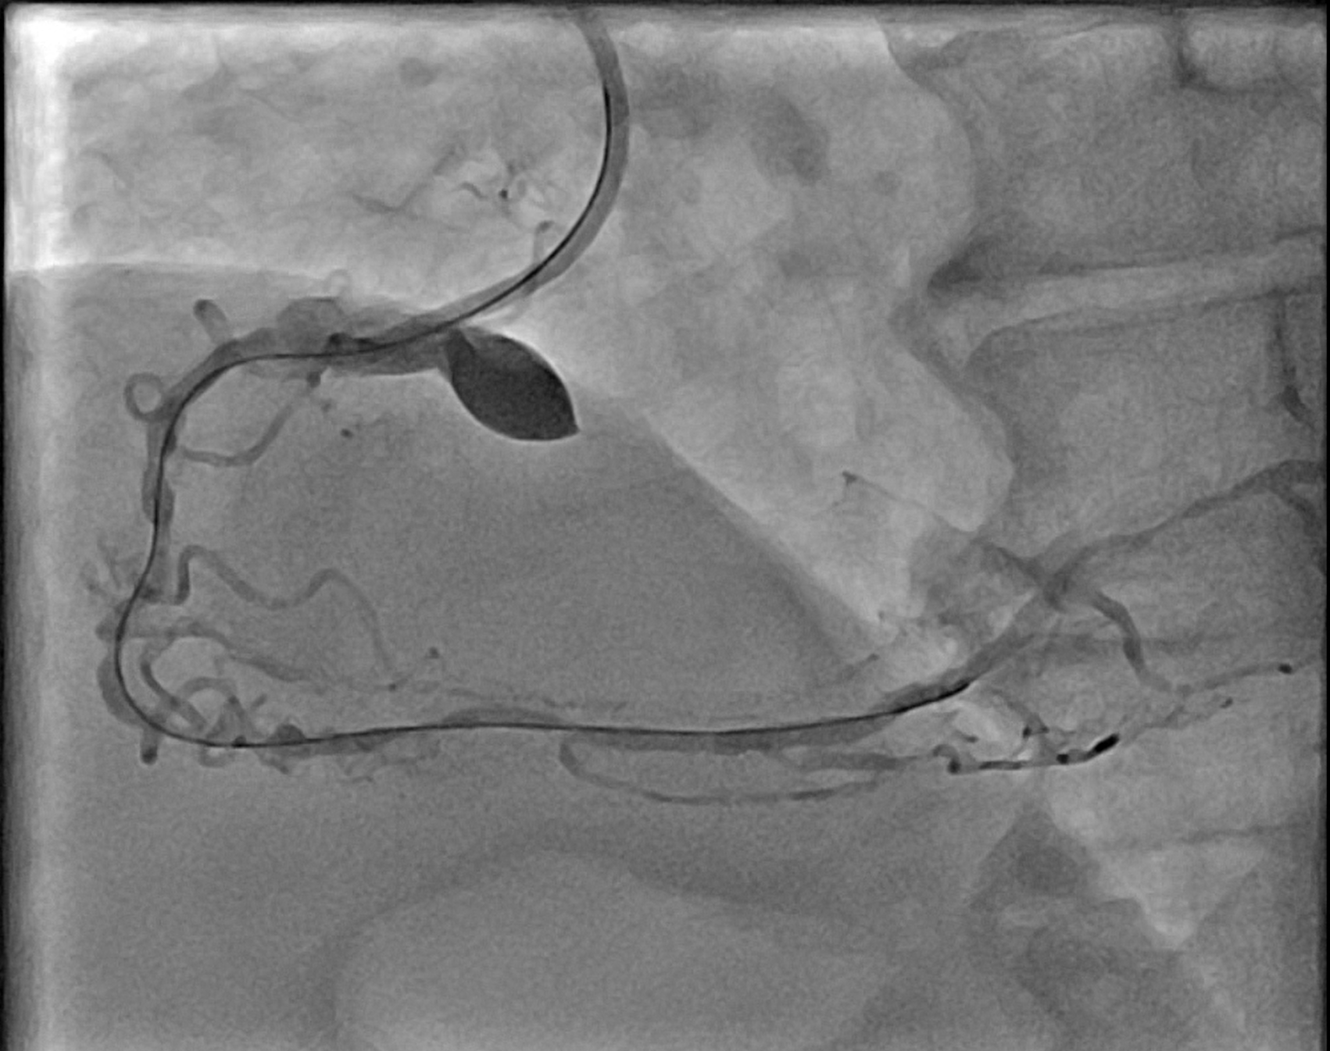

Right radial 6Fr JR 4.0 initially for antegrade RCA CTO attempt, subsequent switched to AL 1.0 for better support. CTO lesion crossed using Gaia Next 3 wire with Finecross microcatheter support, pre-dilatation using SC Sapphire 1.0 ¡¿ 8 mm balloon. However, guide catheter induced aorto-ostial dissection (Dunning Class II) occurred during catheter manipulation and contrast injection. The dissection was promptly recognized and proceed strategy of seal the dissection via ping pong technique. Second access via right femoral 6Fr long sheath due to tortuous iliac artery with JR 4.0, Sion Blue wire crossed to distal RCA. The ostial-proximal lesion is predilated with NC Trek 3.5 ¡¿ 12 mm balloon, then stented with Biofreedom 3.5 ¡¿ 24 mm and post dilate with NC Trek 3.5 ¡¿ 12 mm balloon. The mid to distal RCA lesion is prepared using SC Euphora 2.0 x 15 mm balloon with AL 0.75 catheter and Telescope guide extension support. Further predilate with Lacrosse Aperta 3.0 x 13 mm and NC Sapphire 3.0 x 10 mm balloon. Distal RCA treated with DCB Essential Pro 3.0 ¡¿ 40 mm. Proximal to distal RCA stented with Biofreedom 3.5 ¡¿ 24 mm and Biofreedom 3.5 ¡¿ 36 mm (overlapping from ostial to distal). Final post-dilatation with NC Trek 3.75 ¡¿ 8 mm (mid–distal) and NC Sapphire 4.5 ¡¿ 8 mm (proximal). Final IVUS guidance via AL 0.75 guiding catheter and Telescope guide extension showed good result without hemodynamic compromise. Total contrast 240 mL, fluoroscopy 132 mins.

mov-series-018 aorto ostial RCA dissection.wmv

This case highlights a rare but significant complication of catheter-induced RCA aorto-ostial dissection during PCI for chronic total occlusion. RCA CTO lesions pose technical challenges due to heavy calcification, tortuous course, and limited guide support. In this case, deep seating of the guiding catheter during contrast injection likely precipitated an aorto-ostial tear. Timely recognition and immediate sealing with overlapping DES — guided by IVUS — prevented progression into the ascending aorta and avoided emergent surgical conversion.